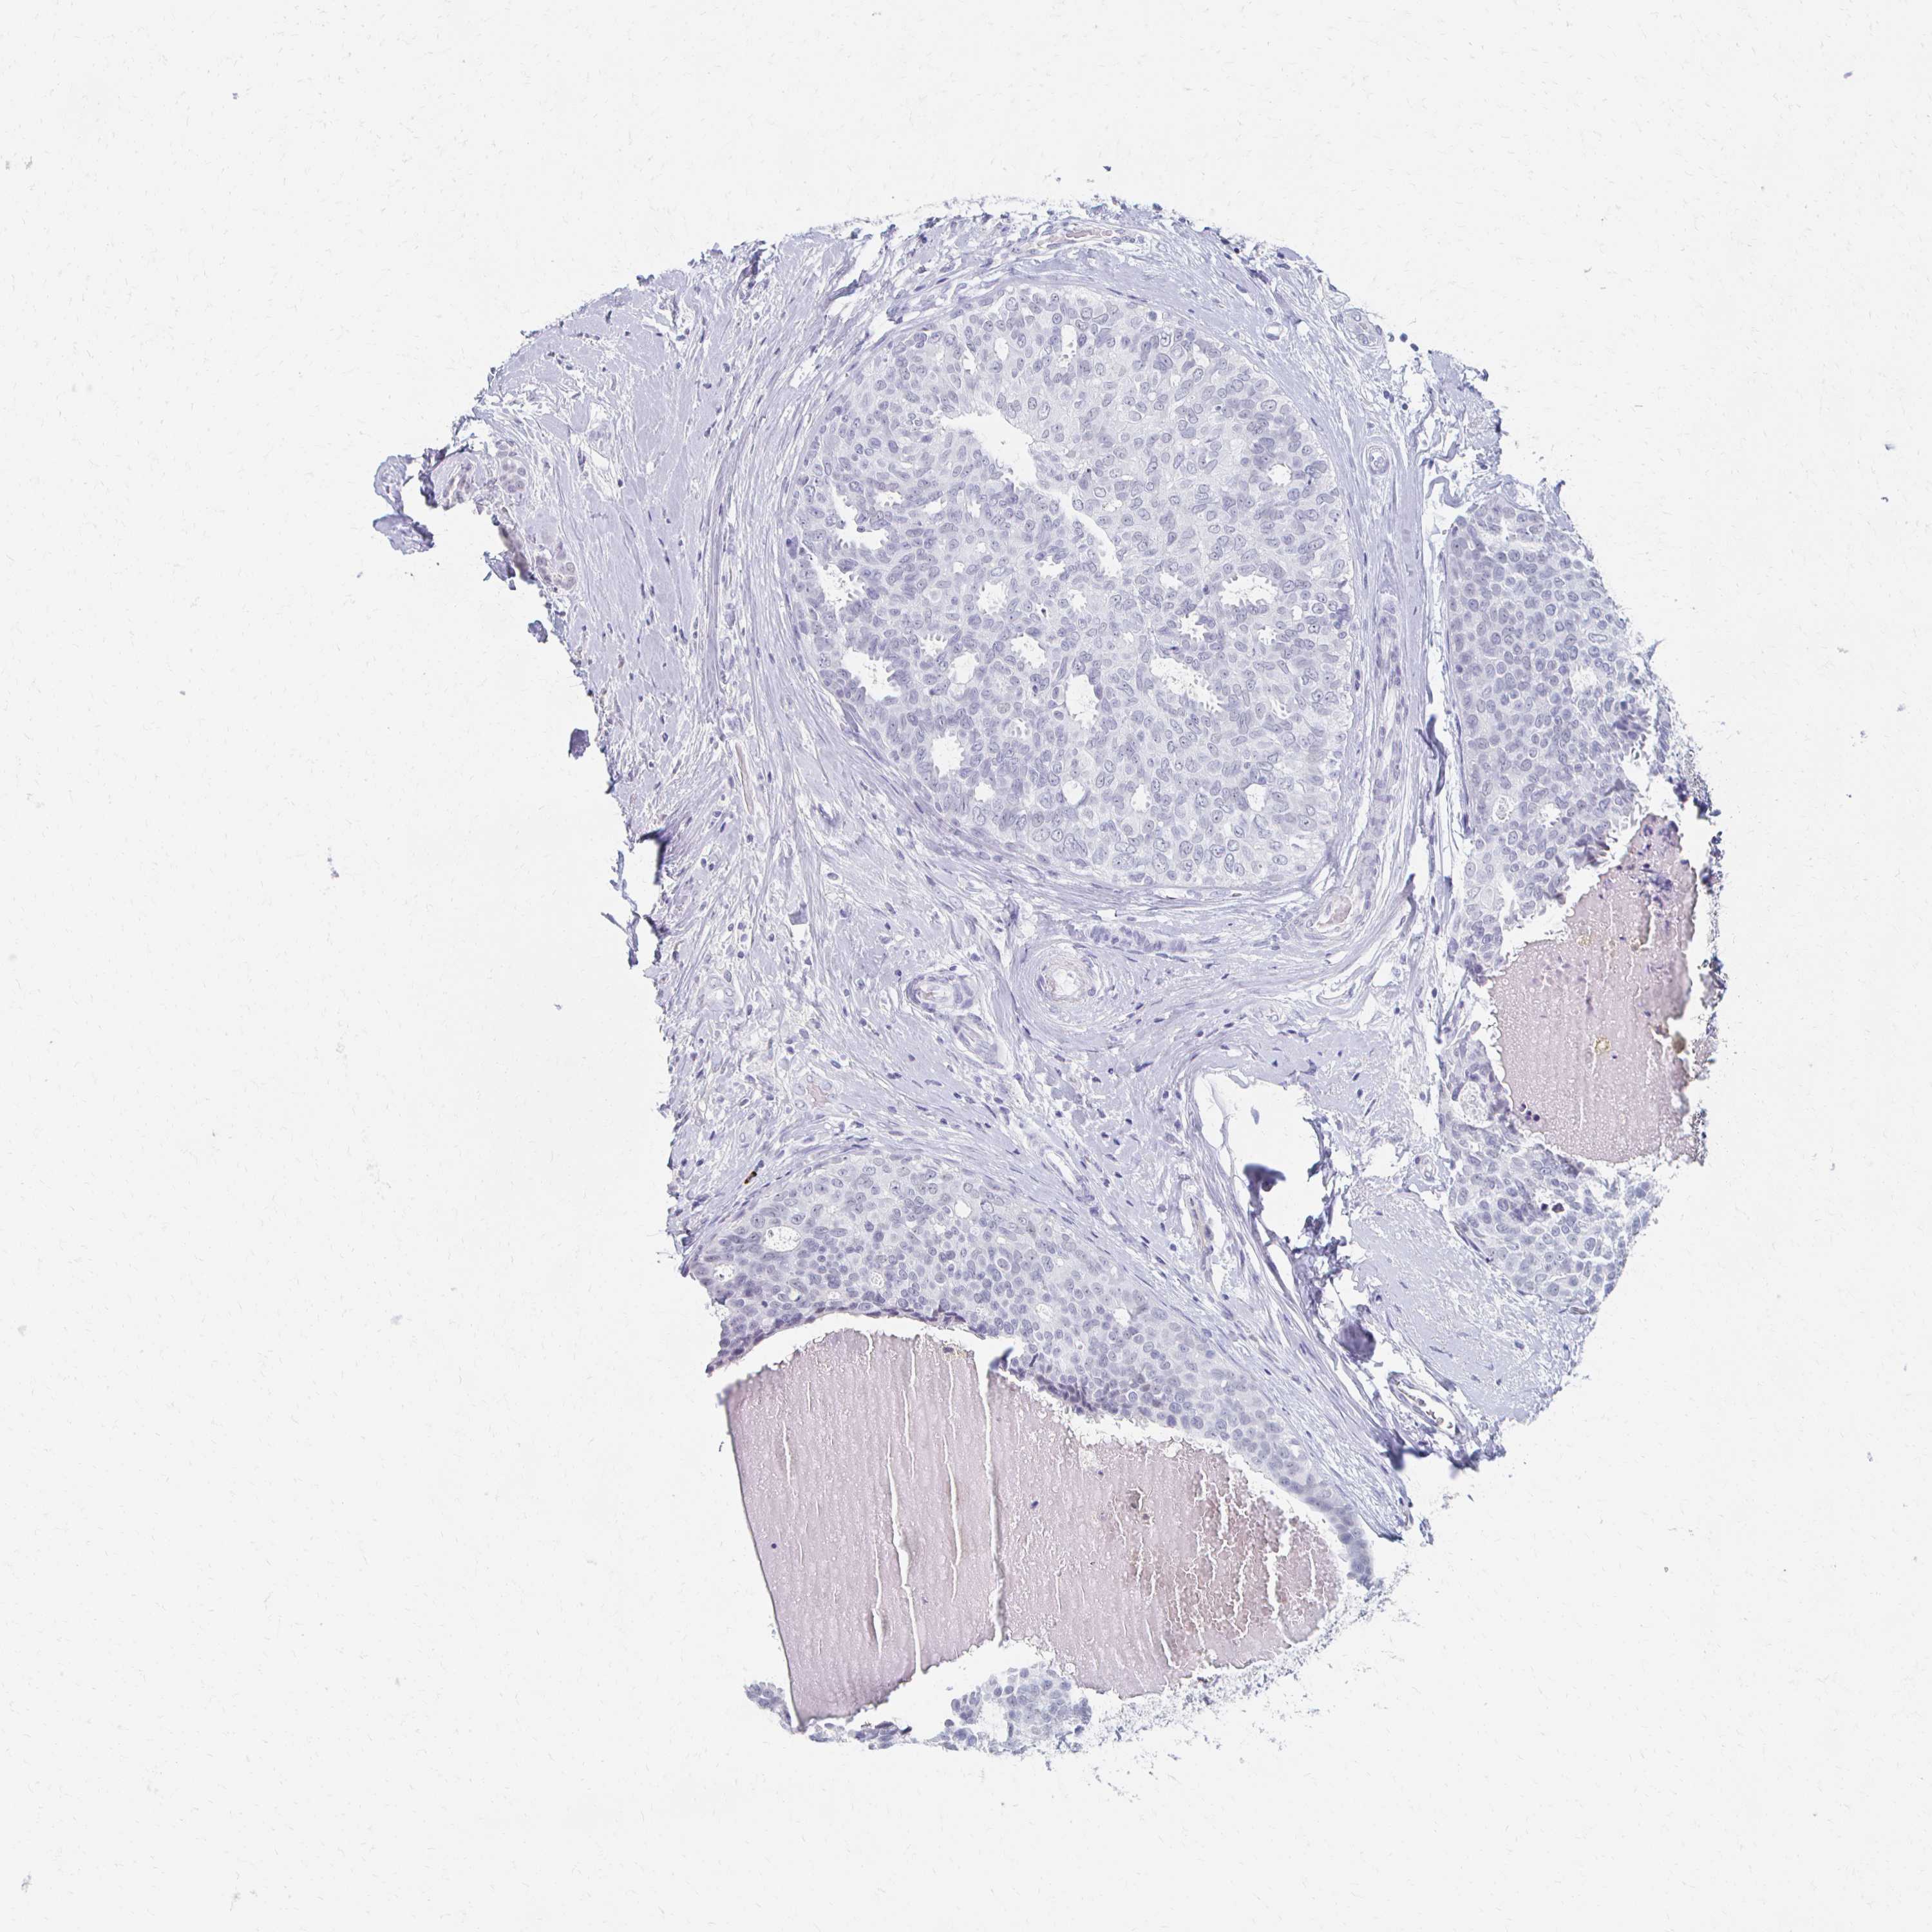

BRCA TCGA BRCA VALIDATION PROTEIN EXPRESSION

Breast cancer

Human cancer